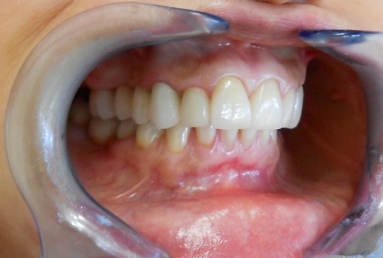

After treatment:

– zirconium/ceramic bridge in the lateral right maxillary area

– two implants and zirconium/ceramic bridge in the lateral left maxillary area

– full ceramic individual crowns in the frontal maxillary area, correcting at the same time the occlusion and the position of the frontal teeth.

– the lower arch was restored with a zirconium/ceramic bridge in the lateral right area and composite esthetic fillings + teeth whitening for the rest of the natural teeth.